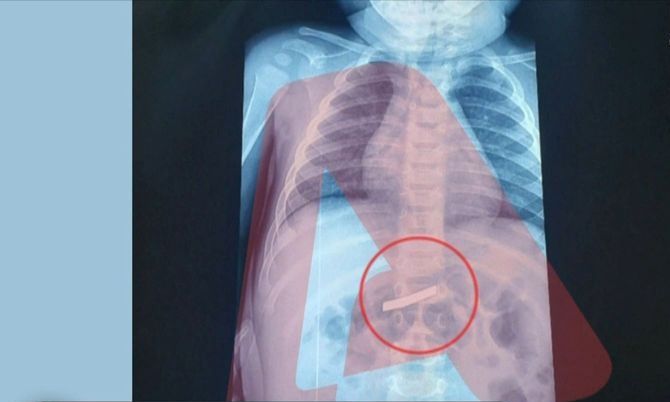

Një ngjarje e pazakontë tronditi Athinën, kur një fëmijë 3-vjeçar u dërgua me urgjencë në spital pediatrik pas gëlltitjes së një brisku rroje. Menjëherë pas mbërritjes, mjekët bënë një grafi që konfirmoi praninë e objektit në stomakun e vogëlushit dhe përcaktoi vendndodhjen e tij.

Kirurgët kryen ndërhyrjen me sukses, duke hequr briskun pa komplikacione, ndërsa fëmija ndodhet tani në gjendje të mirë shëndetësore.